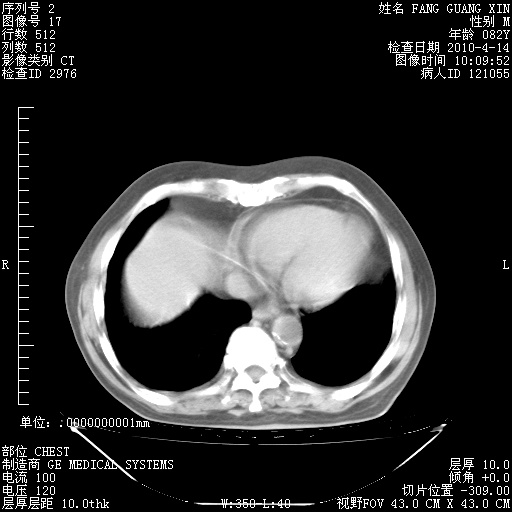

4月28日肺部CT——再次出现类似去年5月9日——透光度降低,(影像科认为)“间质性”改变。

1221483 1 .bmp

1221483 2 .bmp

1221483 3 .bmp

1221483 4 .bmp

1221483 5 .bmp

4月28日肺部CT——再次出现类似去年5月9日——透光度降低,“间质性”改变。